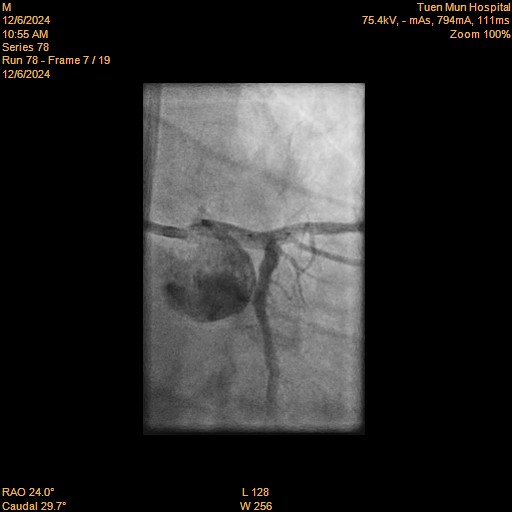

Relevant Catheterization Findings

LMS: Normal LAD: Occluded from proximal segment onwards, receiving collaterals from right system LCX: Moderate disease distally RCA: Dominant. Minor disease

caudal.avi